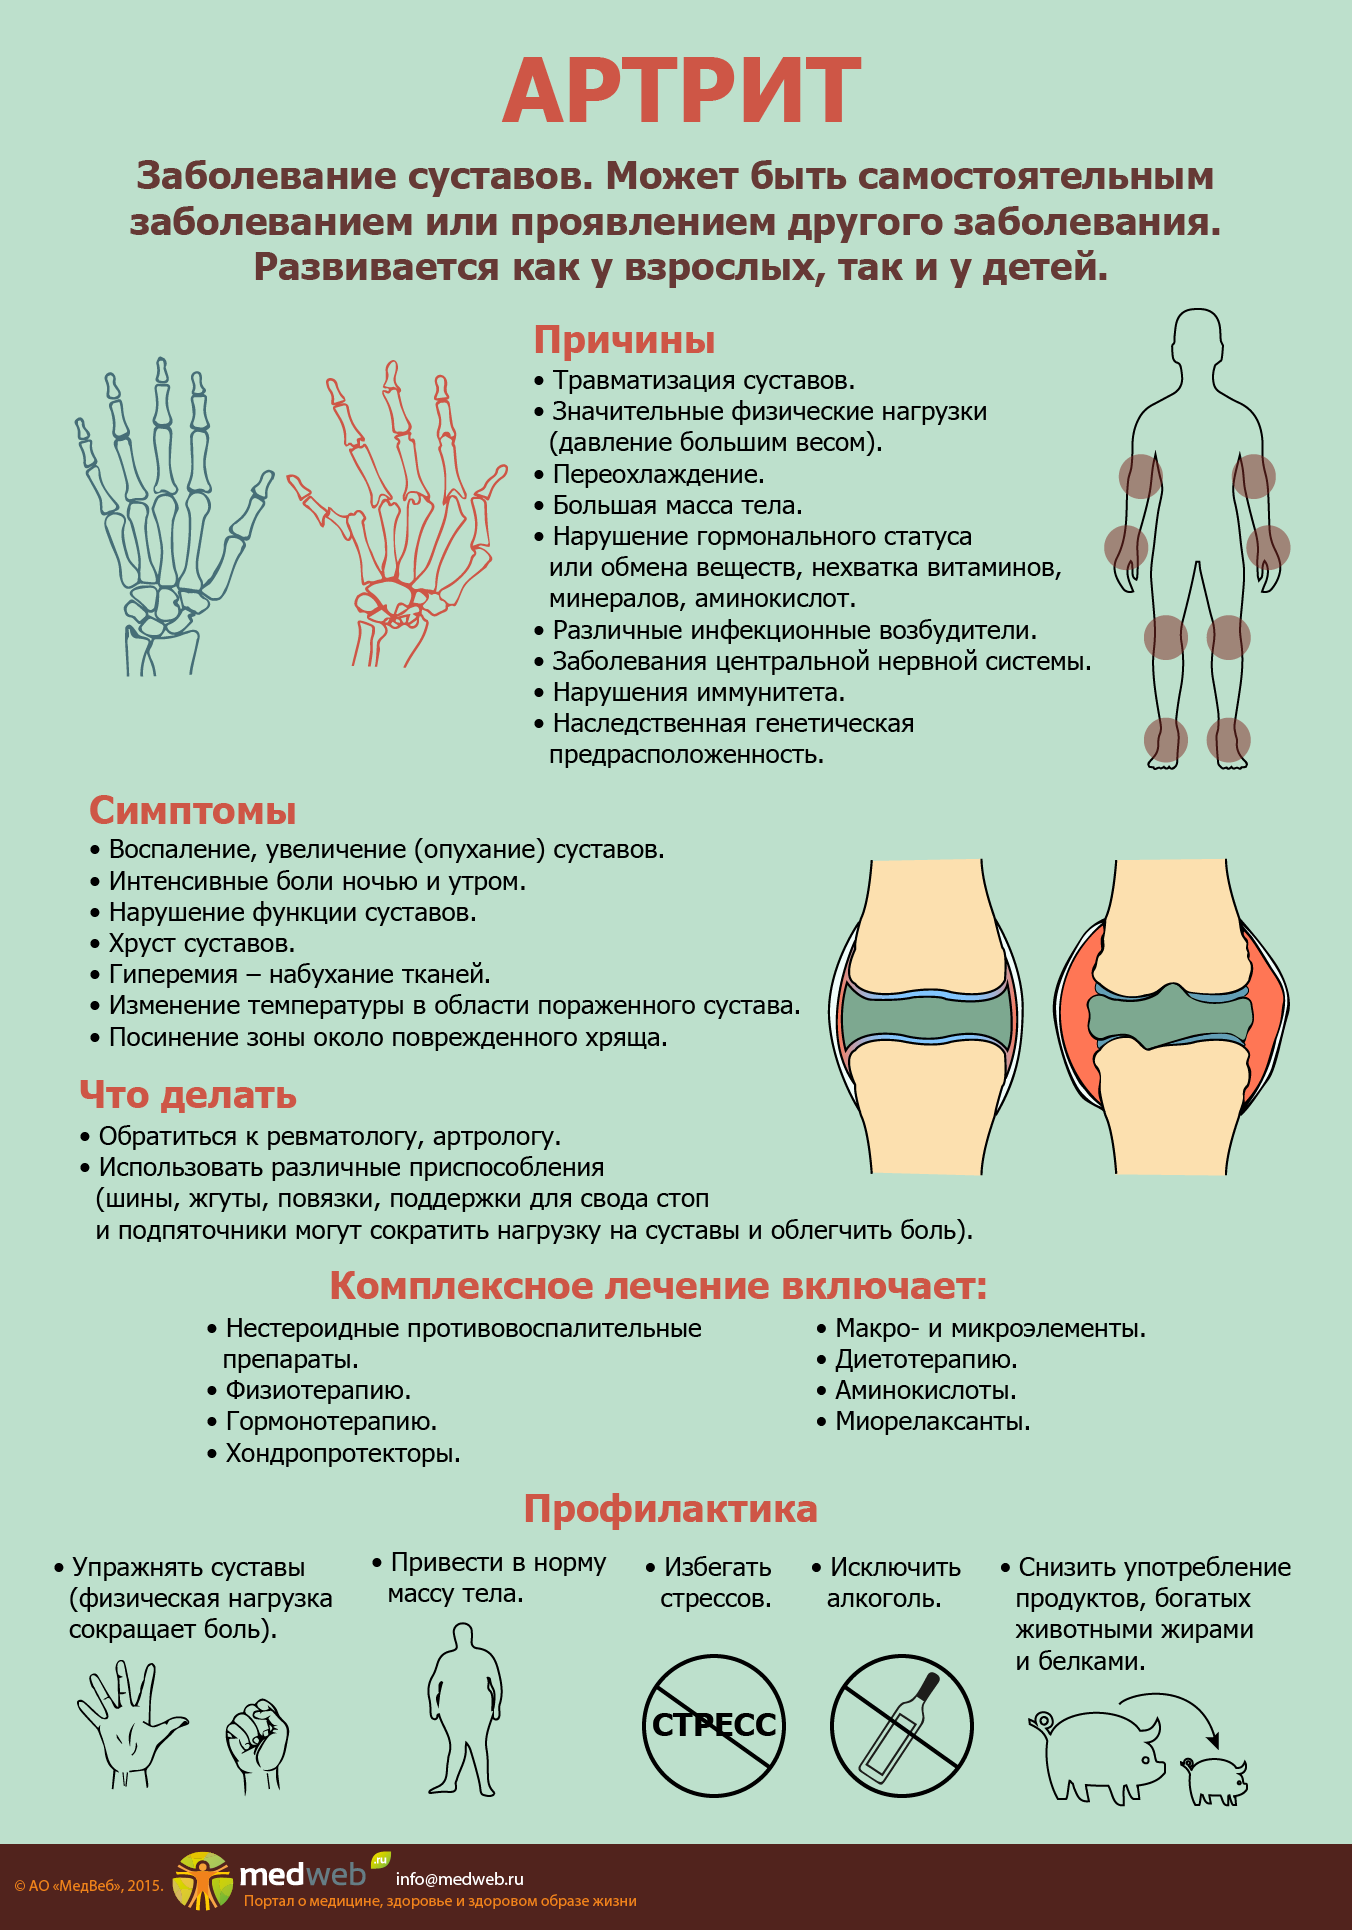

Причины артроза кистей рук

Воздействие различных внешних и внутренних факторов может быть причиной артроза:

- наследственные особенности строения хрящевой ткани – она может быстро разрушаться от воздействия разных факторов;

- пожилой и старческий возраст – разрушению суставного хряща способствует возрастные изменения кровообращения и снижение обмена веществ;

- гормональная патология – особенно часто проявляются у женщин при снижении гормонального фона, в том числе, возрастном, при климаксе;

- физические нагрузки – постоянные длительные мелкие работы руками, сопровождающиеся микротравмированием; особенно страдают женщины из-за высоких нагрузок по дому;

- последствия травм кисти – переломов, вывихов, ушибов;

- последствия остро и хронически протекающих артритов (воспалительных процессов) различного происхождения.

Под воздействием различных внешних и внутренних причин в организме происходят изменения: снижается объем синовиальной жидкости, питающей хрящ. Покрывающий головки суставных поверхностей хрящ постепенно истончается, теряет эластичность, растрескивается и разрушается. Это приводит к разрастанию костной и соединительной ткани, изменению формы и снижению функции мелких суставчиков. Процесс сопровождается постепенно нарастающим болевым синдромом.

Дисплазия. Основные причины этой патологии – изменение структуры коллагена, вызванное генетическими причинами, и нехватка компонентов, из которых строится соединительная ткань. Заболевание проявляется частыми вывихами, искривлением позвоночника, пролапсом митрального клапана, близорукостью, плоскостопием. Хруст в суставах также может быть одним из симптомов.

Артрит. Воспалительный процесс в суставе приводит к расслоению, истончению и трещинам хрящевой ткани. Если заболевание не лечить, изменения со временем затрагивают и кость: на ней появляются наросты, уплотнения и шипы. Далее происходит деформация кости, из-за чего возникают отеки и сильные боли даже в состоянии покоя.

- Артрит (воспаление одного или нескольких суставов). Изменения в хрящевой ткани при артритах проявляется трещинами, расслоением, истончением, что приводит к появлению скрипения при движениях в суставе. Кроме того, хруст и треск связаны с изменениями в костной ткани — появлением уплотнений, шипов, наростов.